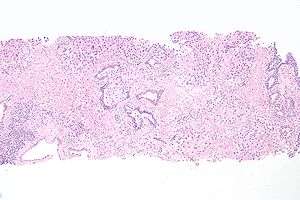

| Histopathology of urothelial carcinoma of the urinary bladder. Transurethral biopsy. H&E stain. | |

Histopathology of urothelial carcinoma of the urinary bladder, showing a nested pattern of invasion. Transurethral biopsy. Hematoxylin and eosin.

Histopathology of urothelial carcinoma of the urinary bladder.